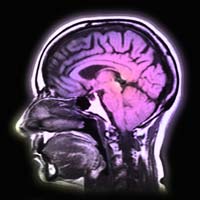

Inside the Teenage Brain: Just what¼s going in there?  A look at how science may help explain the mysteries of the teen years.

The Teen Brain is a Work in Progress

Neuroscientists and psychologists discuss their findings; overviews of recent research; and an interactive illustration of the brain.